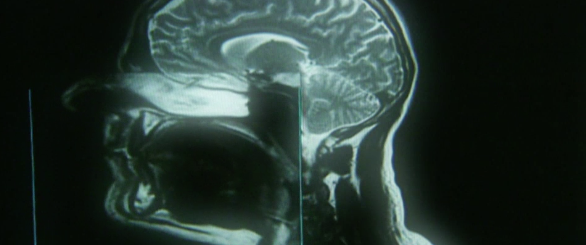

Czy mleko matki może być cudownym remedium na raka? Co powoduje chroniczne zmęczenie, na które nie ma lekarstwa? Czy antybiotyki sprawią, że wytworzą się super bakterie, które już niedługo będą główną przyczyną przedwczesnych zgonów? I w końcu - kiedy naprawdę następuje śmierć i kiedy można pobrać narządy do przeszczepu? To tylko kilka pytań, które dokumentaliści zadają ekspertom, lekarzom i genetykom.